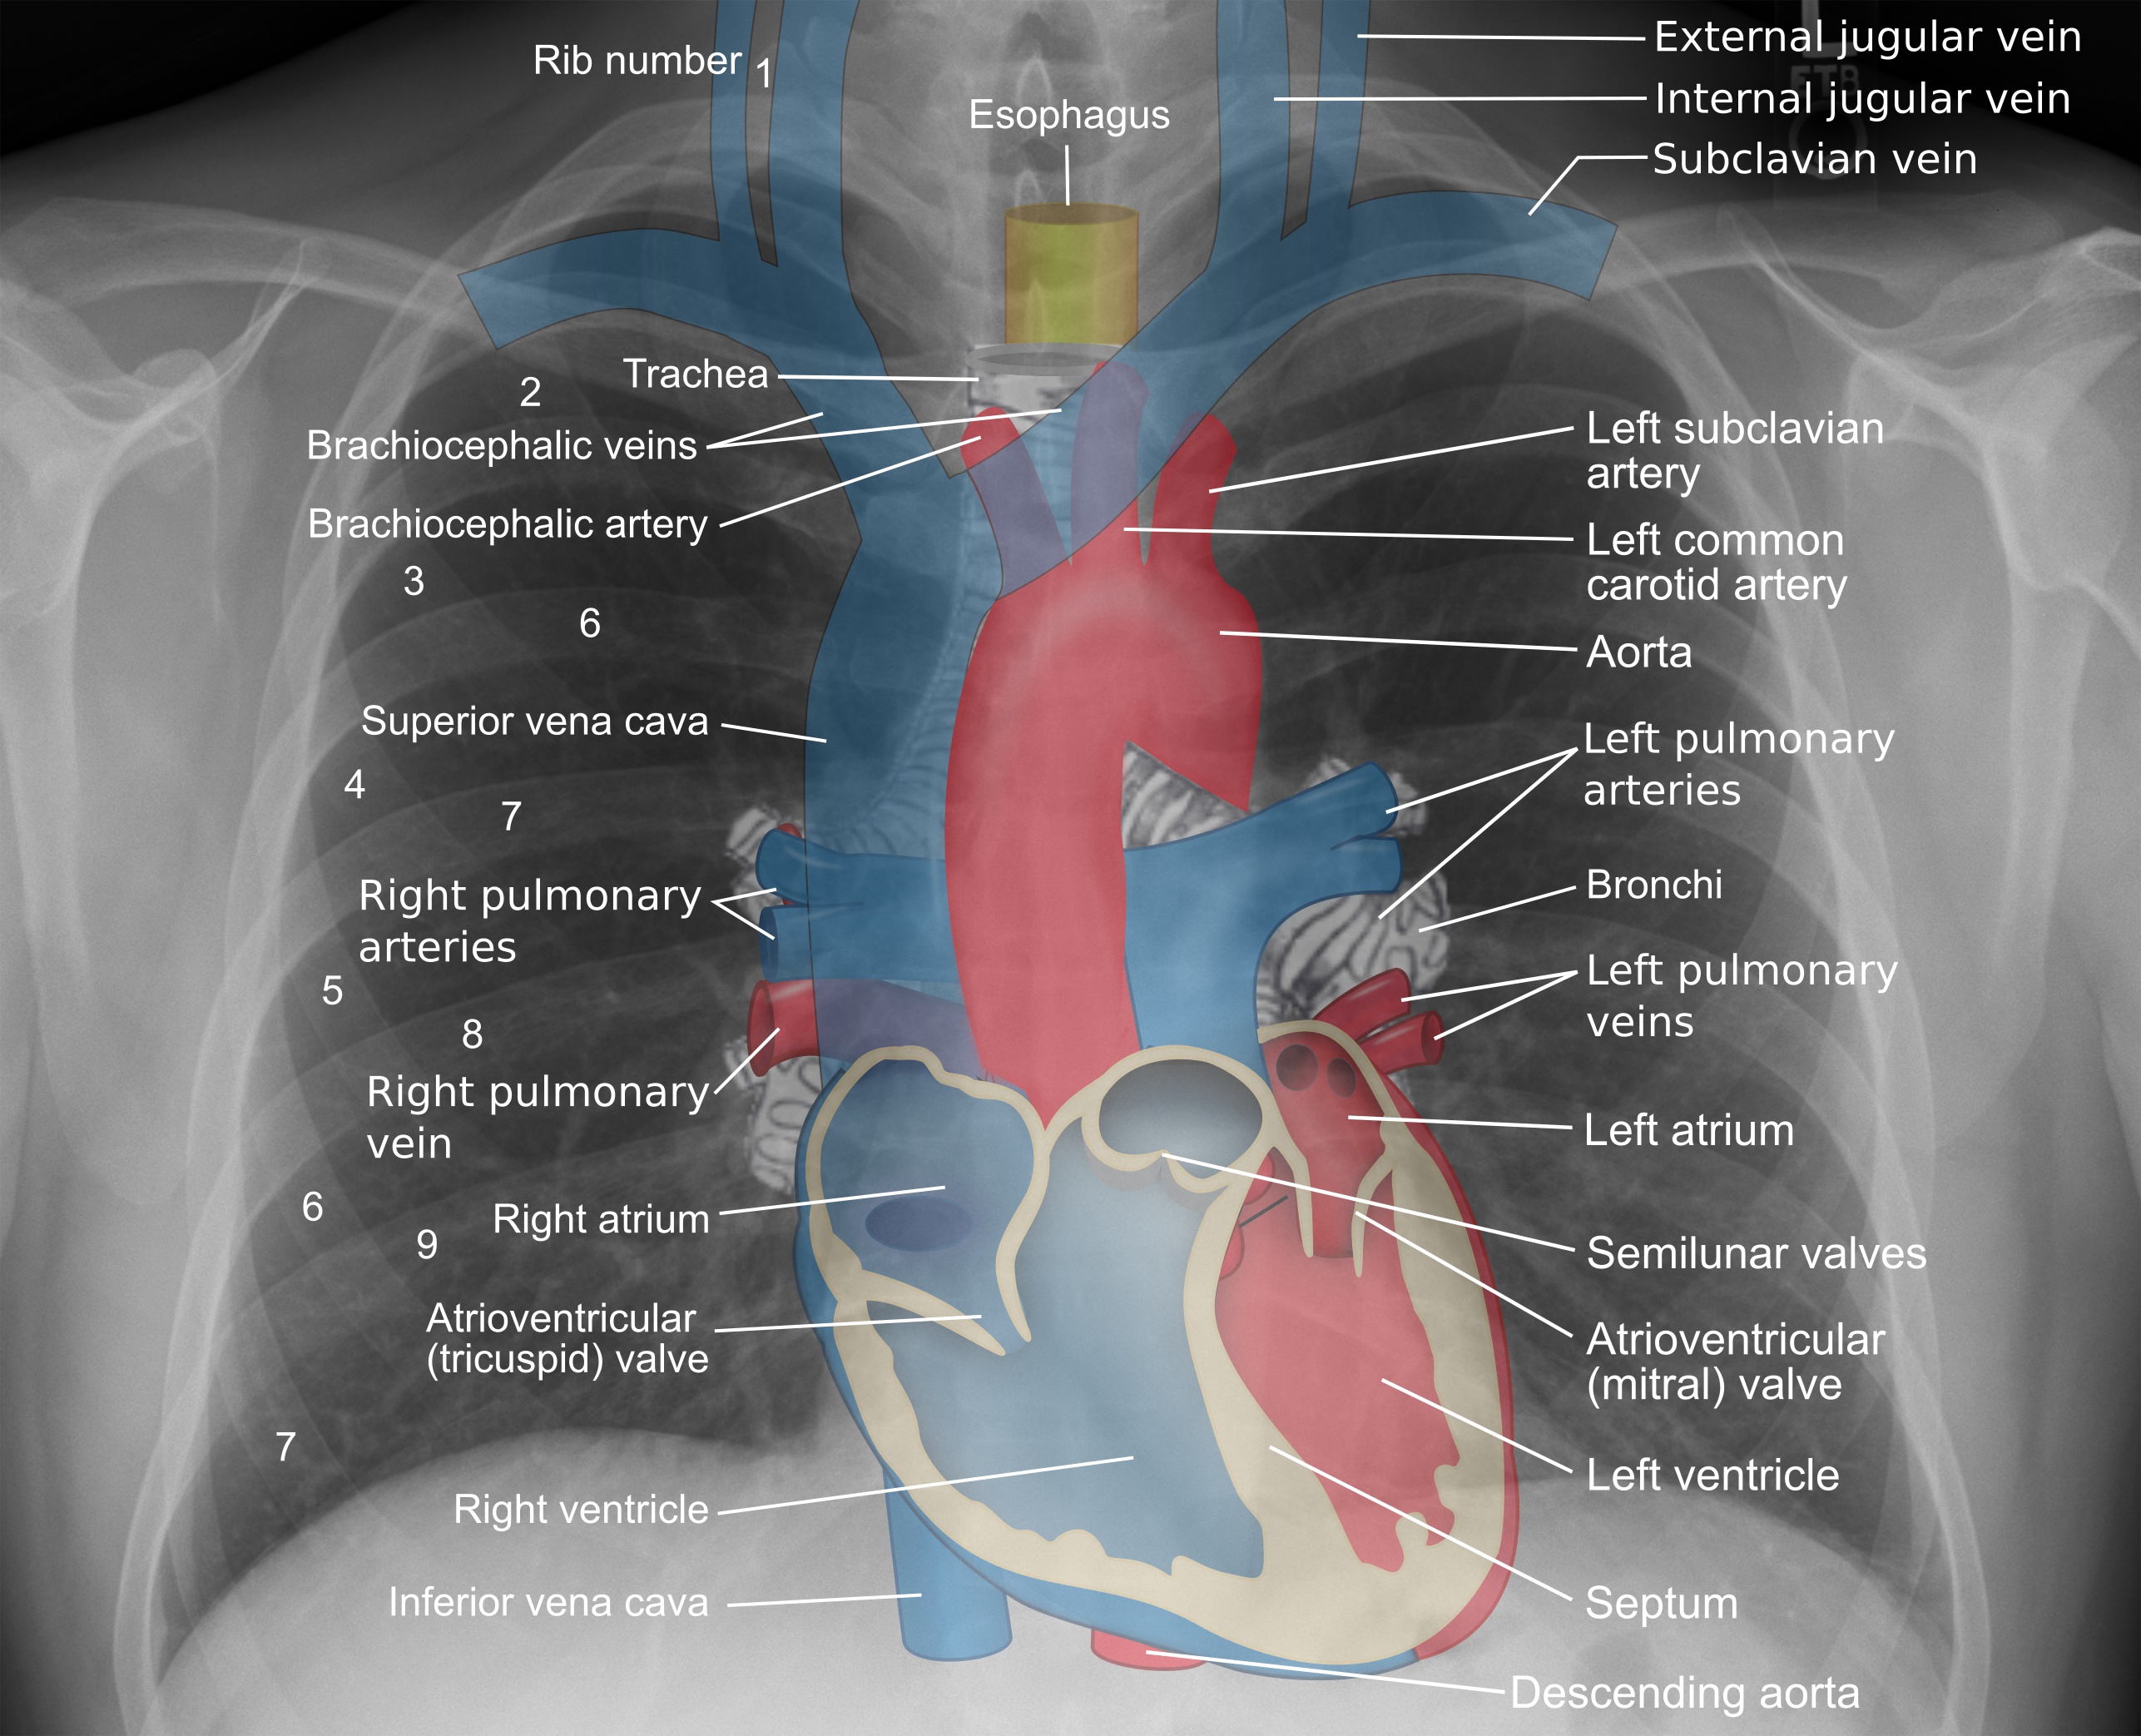

가슴세로칸은 가슴 내부에 위치하며, 가슴막에 의해 오른쪽과 왼쪽이 닫혀 있는 공간이다. 가슴벽, 폐, 척추에 의해 둘러싸여 있으며, 위세로칸과 아래세로칸으로 나뉜다. 위세로칸은 위가슴문에서 복장뼈각까지, 아래세로칸은 복장뼈각에서 가로막까지이며, 심장막을 기준으로 앞, 중간, 뒤세로칸으로 세분된다. 가슴세로칸에는 기관, 혈관, 신경, 림프절 등 다양한 구조물이 위치하며, 세로칸종양, 세로칸염, 세로칸기종, 세로칸확장 등 다양한 임상적 문제를 야기할 수 있다.

2. 해부학

가슴세로칸은 가슴 안에 위치하며 좌우 가슴막으로 닫혀 있다. 앞쪽은 가슴벽, 양쪽은 폐, 뒤쪽은 척추로 둘러싸여 있으며, 앞쪽 복장뼈에서 뒤쪽 척추까지 뻗어 있다.[21][22] 가슴세로칸은 폐를 제외한 가슴의 모든 장기를 포함하며,[22][23] 목의 성긴결합조직과 이어진다.

가슴세로칸은 위세로칸과 아래세로칸으로 나뉜다.- '''위세로칸'''(상종격동)은 위가슴문에서 시작하여 복장뼈각 높이에서 끝난다.

- '''아래세로칸'''(하종격동)은 위세로칸이 끝나는 높이에서 시작하여 가로막에서 끝난다. 아래세로칸은 심장막을 기준으로 다시 세 부위로 나누어진다.

- '''앞세로칸'''(전종격동)은 심장막 앞쪽이다.

- '''중간세로칸'''(중종격동)은 심장막과 그 안 구조물이다.

- '''뒤세로칸'''(후종격동)은 심장막 뒤쪽의 공간을 나타낸다.[24]

2. 3. 위세로칸

위세로칸은 위가슴문에서 복장뼈각과 T4 등뼈를 잇는 가상의 평면까지의 공간이다.위세로칸의 경계는 다음과 같다.

2. 4. 1. 앞세로칸

2. 4. 2. 중간세로칸

심장막에 의해 경계가 지어진다. 심장막에는 생명 유지에 중요한 기관들이 들어 있으며 장막심장막과 섬유심장막으로 나뉜다.[22];내용물